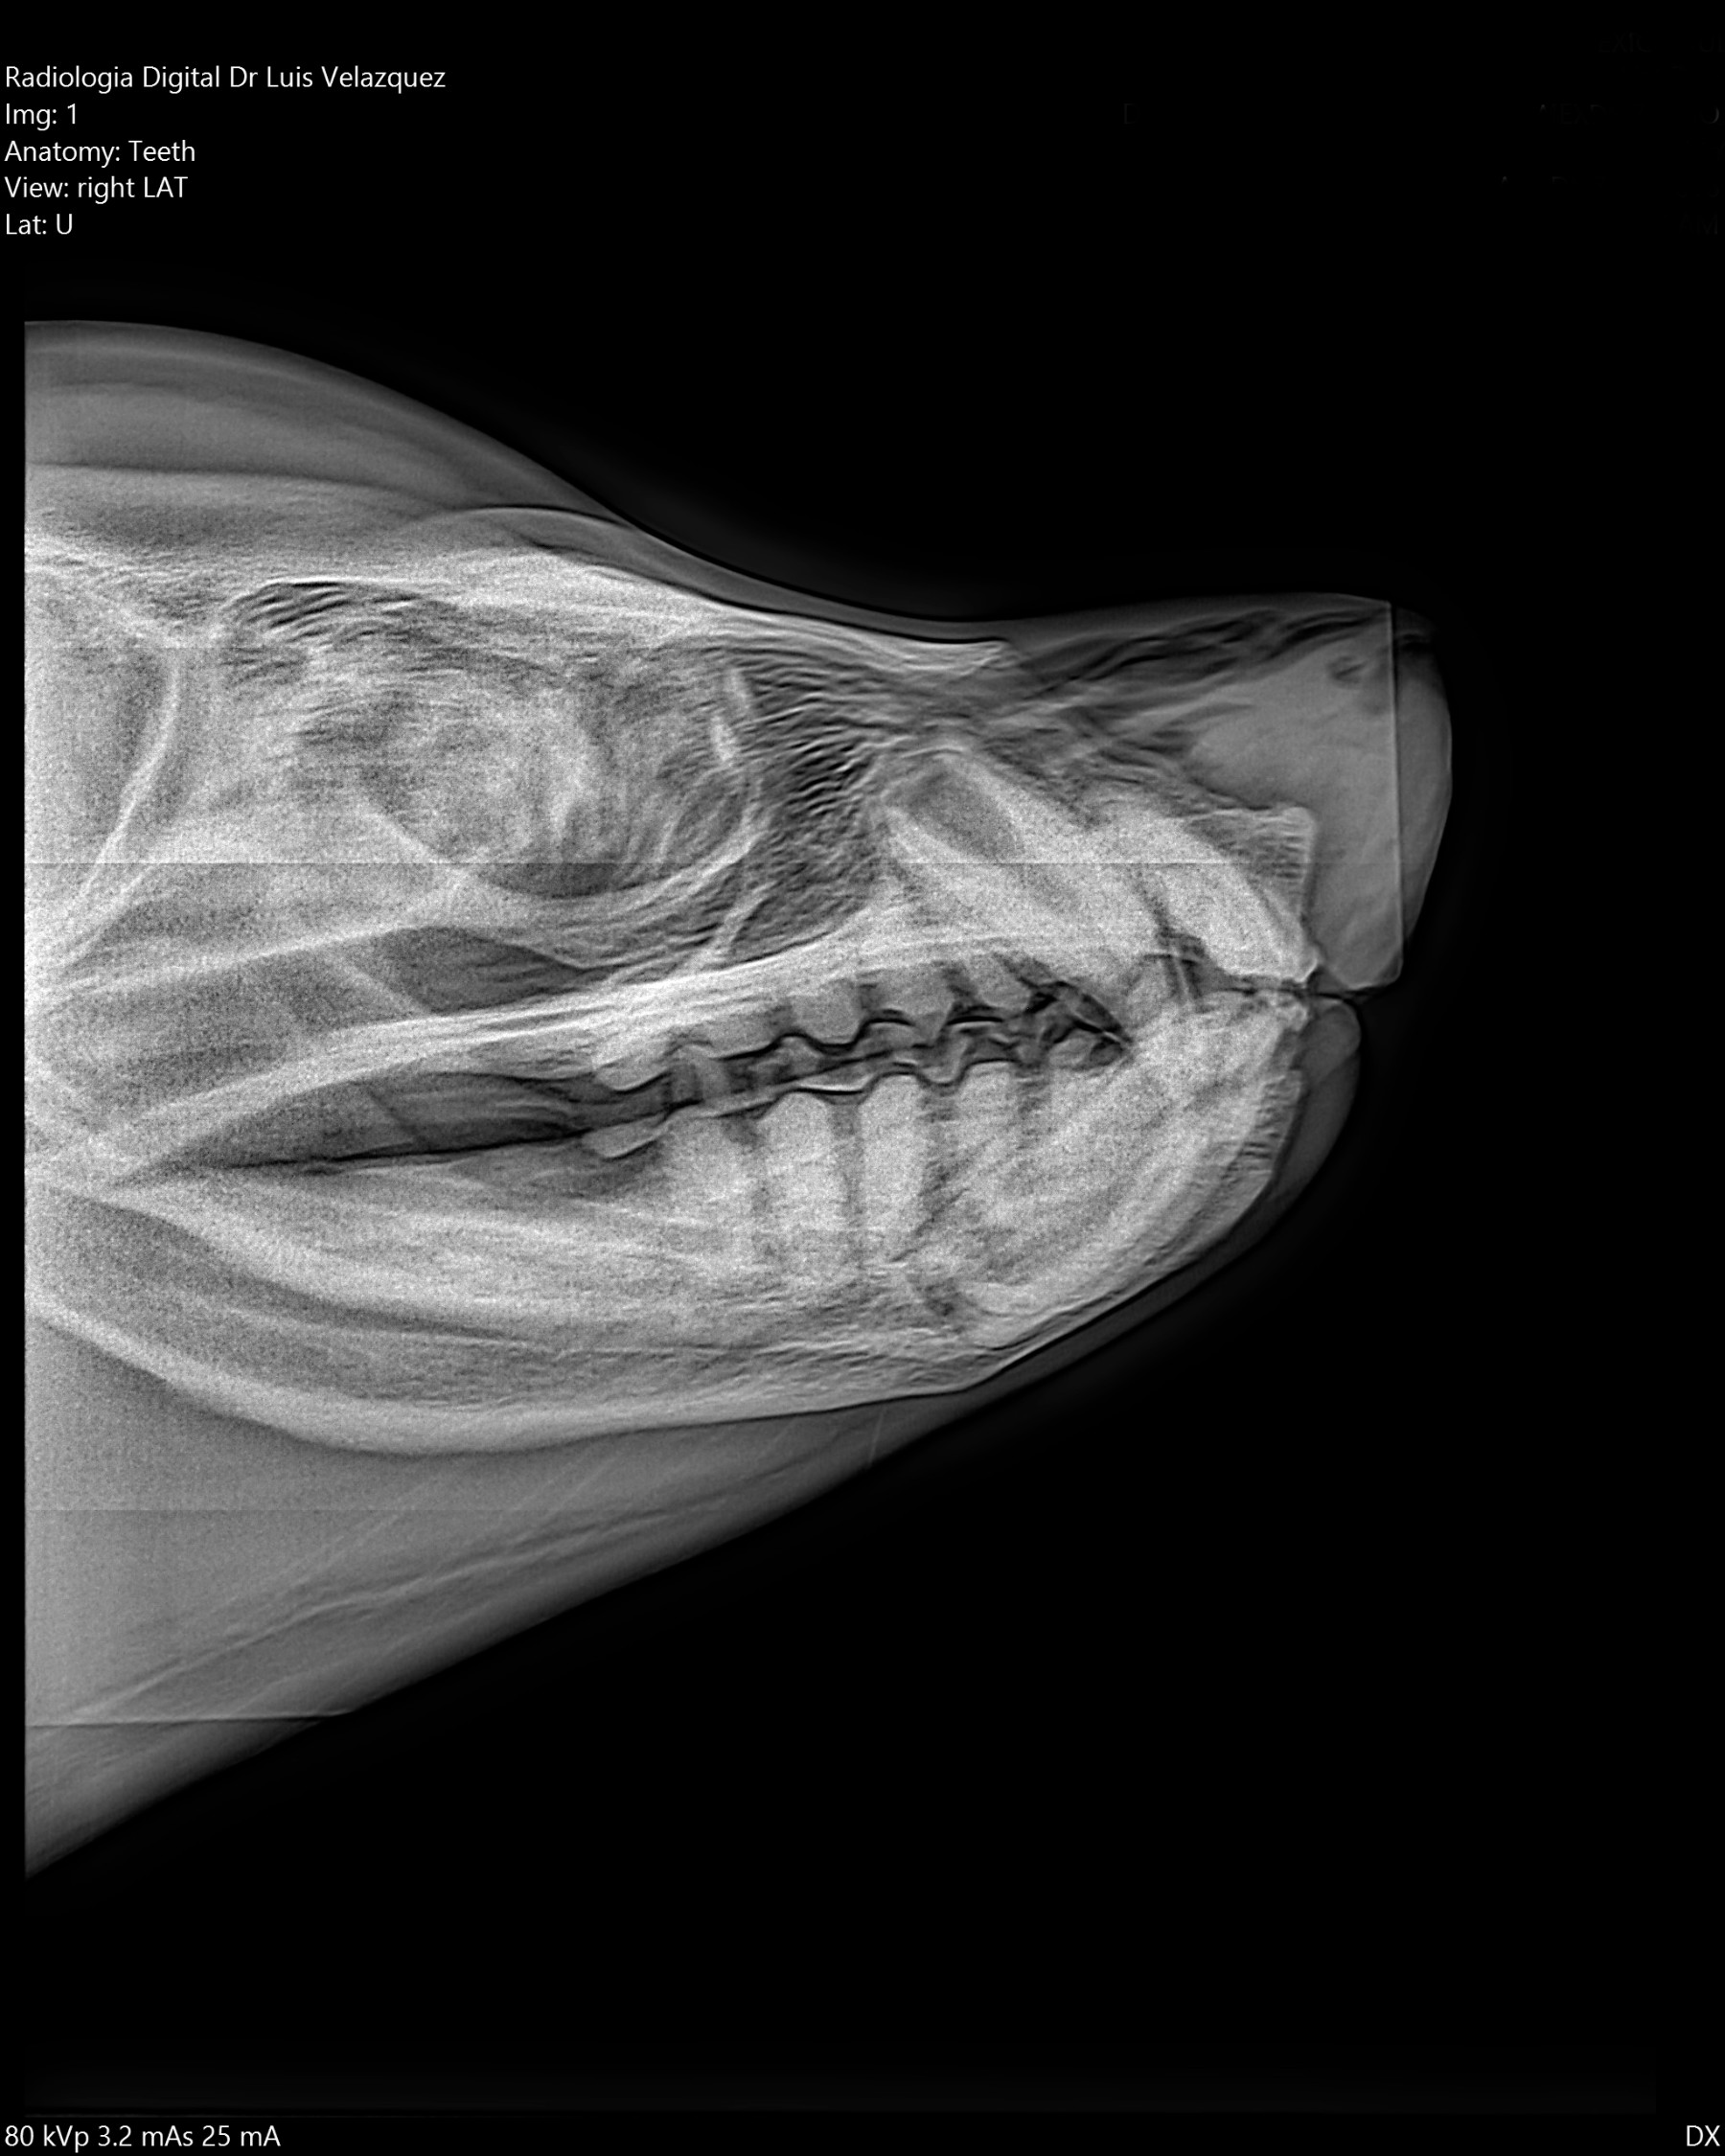

Radiología Digital como Herramienta Complementaria en el Dictamen de Bienes Muebles

Desde el descubrimiento de los rayos “X” y las placas radiográficas por Wilhelm Conrad Roentgen y su posterior difusión a través de la Asociación Físico médica de Wurzburg el 28 de diciembre de 1895, que fue la primera asociación que habló de los nuevos rayos que podían penetrar el cuerpo y fotografiar los huesos, ha habido muchos cambios tanto en la forma de obtener, procesar e incluso en la forma de visualizar, manejar y almacenar las placas radiográficas.